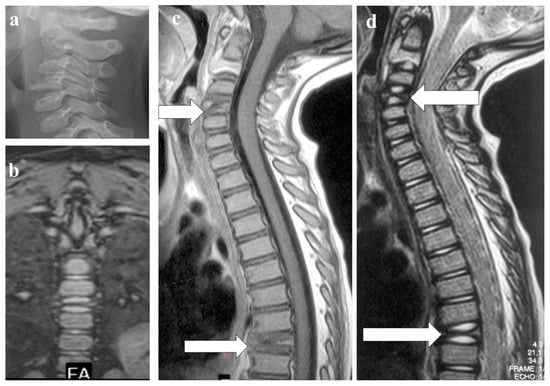

- Sureka, J.; Samuel, S.; Keshava, S.; Venkatesh, K.; Sundararaj, G. MRI in patients with tuberculous spondylitis presenting as vertebra plana: A retrospective analysis and review of literature. Clin. Radiol. 2013, 68, e36–e42. [Google Scholar] [CrossRef]

- Kaila, R.; Malhi, A.M.; Mahmood, B.; Saifuddin, A. The Incidence of Multiple Level Noncontiguous Vertebral Tuberculosis Detected Using Whole Spine MRI. J. Spinal Disord. Tech. 2007, 20, 78–81. [Google Scholar] [CrossRef]

- Haghighatkhah, H.; Jafroodi, Y.; Taheri, M.S.; Pourghorban, R.; Dehkordy, A.S. Multifocal Skeletal Tuberculosis Mimicking Langerhans Cell Histiocytosis in a Child: A Case Report with a Long-Term Follow-Up. Iran. Red. Crescent. Med. J. 2015, 17, e19942. [Google Scholar] [CrossRef] [PubMed]